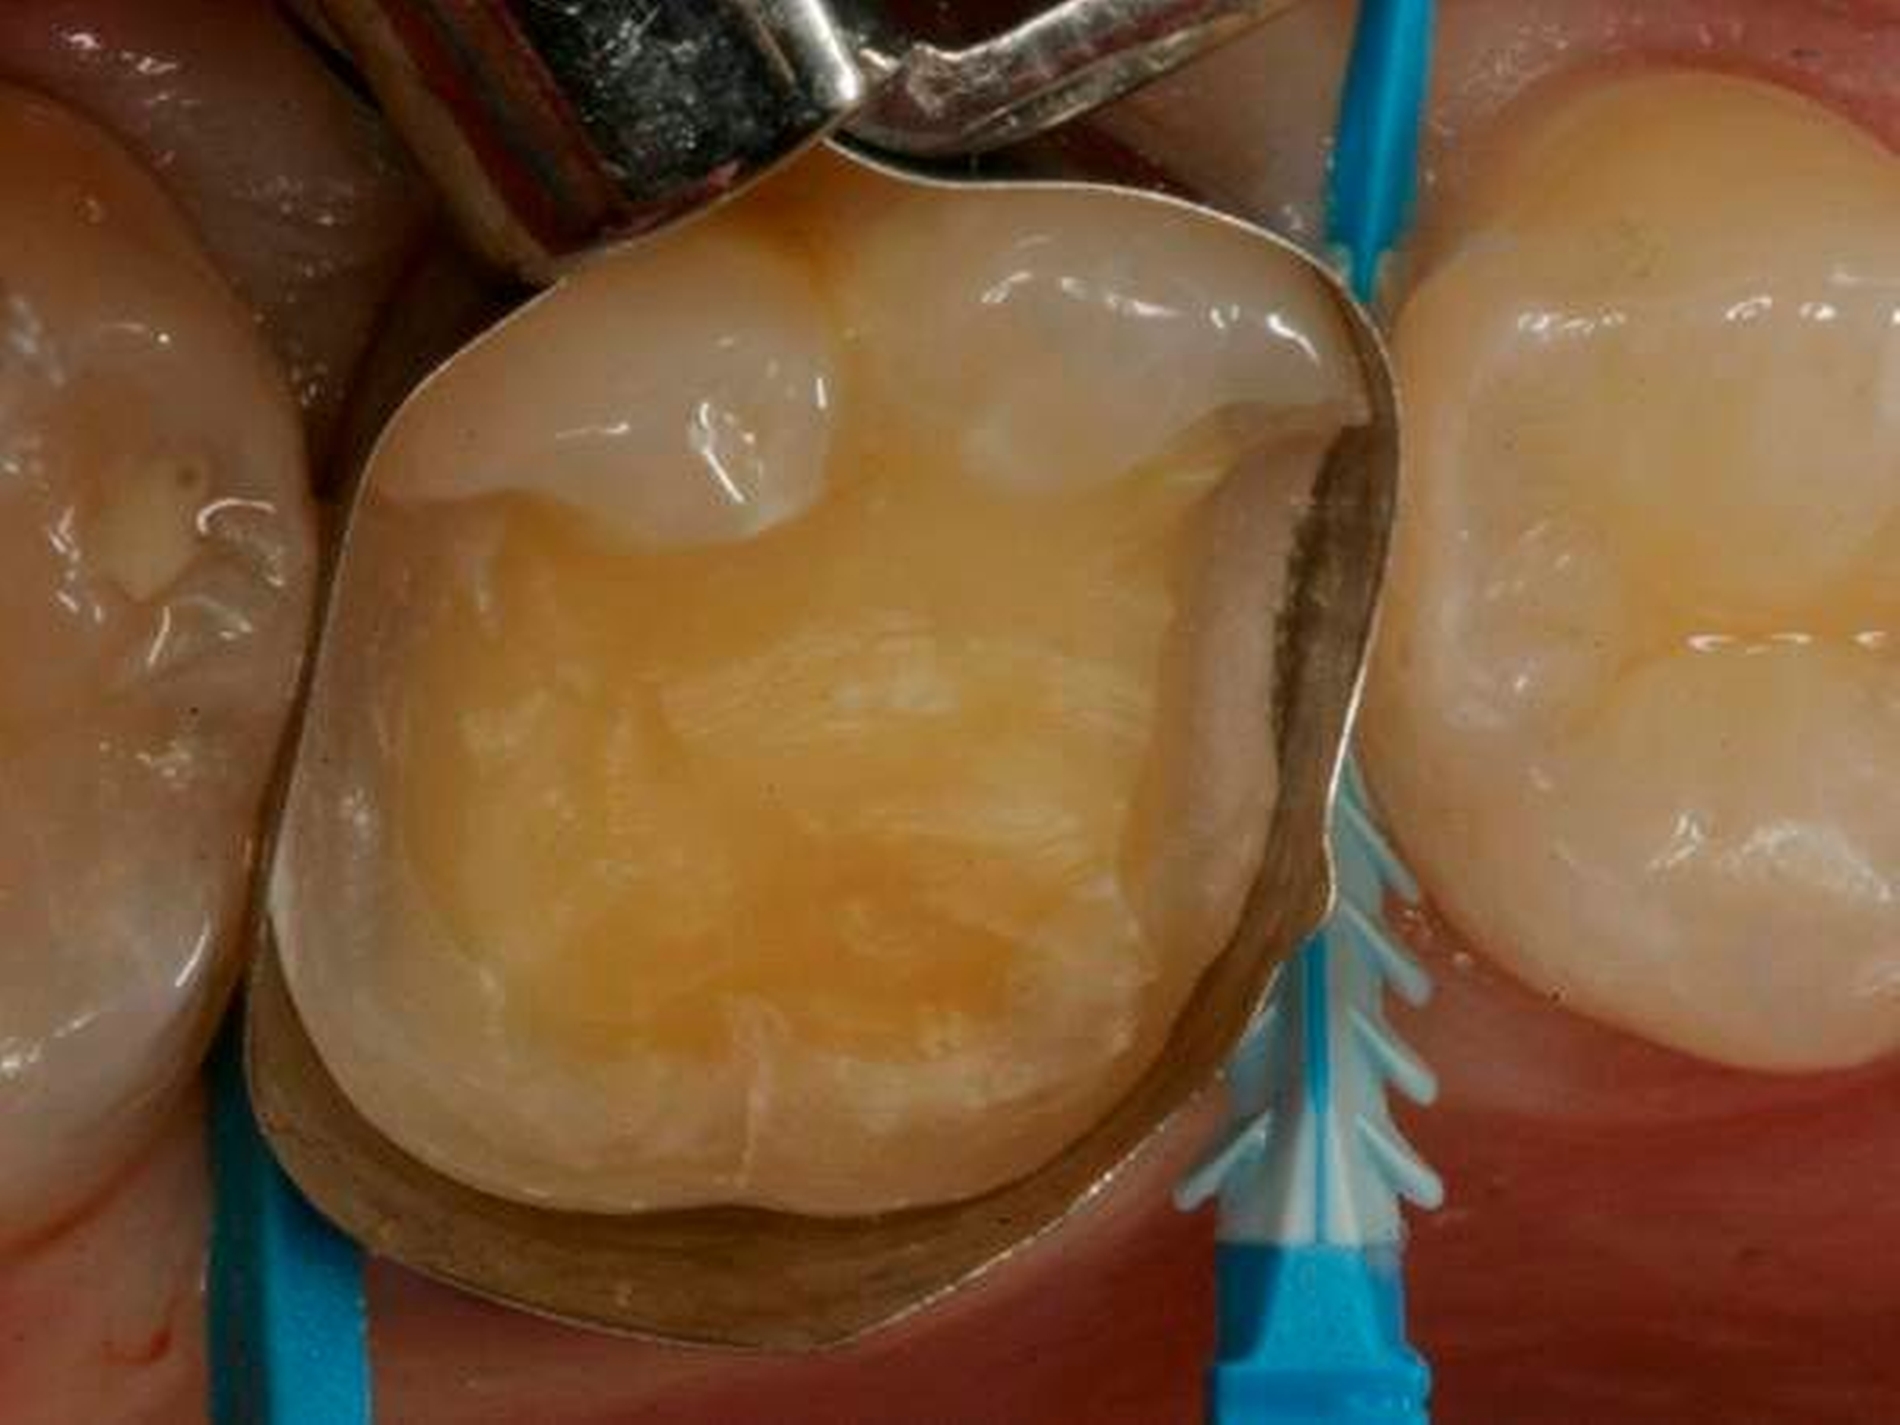

Die Abbildung 2 zeigt die nachpräparierte und mit einem zirkulären, anatomischen Tofflemire-Band (Kerr) isolierte Kavität. Die approximale Abdichtung und Separation erfolgten mithilfe eines Compositight Fusion Wedges (Garrison) mesial und eines G-Wedges (Garrison) distal.

Zur adhäsiven Vorbehandlung wurde ein Universaladhäsiv (Scotchbond Universal, 3M) verwendet. Aufgrund der vorliegenden Überreizung des großflächig freigelegten okklusalen Dentins sollte hier selbstkonditionierend [Marchesi et al., 2014] vorgegangen werden.

Die zusätzliche Schmelzätzungsoption der Universaladhäsive stellte dort eine optimale adhäsive Anbindung sicher [Loguerico et al., 2015; Takamizawa et al., 2016; Takamizawa et al., 2015]. Da eine spätere Neuversorgung nicht unwahrscheinlich erschien, erfolgte die Applikation eines weiß-opak-eingefärbten Flow-Komposits (Venus Diamond Flow, Kulzer) [Ernst, 2014] auf die approximalen und palatinalen Präparationsgrenzen (Abbildung 3). Dies erleichtert eine spätere Detektion und damit eine potenzielle Wiederentfernbarkeit deutlich.